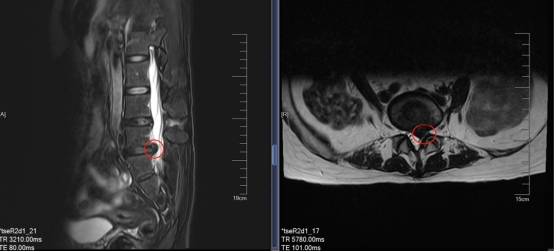

▲术前MRI检查

结合相关检查结果,脊柱外科主任医师吴梅祥发现宁女士腰5-骶1椎间盘突出,进而引起腰5椎体的位置改变,出现高于骶骨的现象。由于长期感到疼痛,宁女士不自觉地向左侧倾斜,还造成了脊柱侧弯。

“从力学上讲,腰4-腰5及腰5-骶1椎间盘所承受的压力最大,而其后韧带也相对狭窄,更容易受伤”吴梅祥主任解释,椎间盘的退行性改变本就会压迫周围组织和神经,加之持续劳累或突然受伤,就会使神经根及周围组织水肿,进一步使压迫加重。